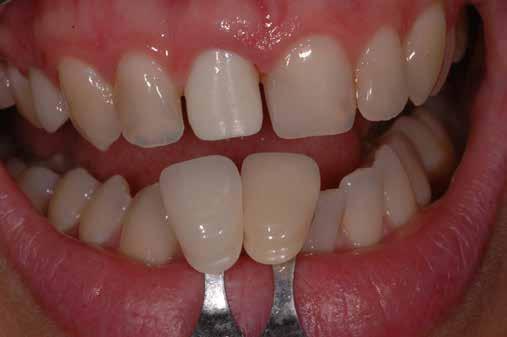

A 2020 januárjában elkezdett kezeléssorozat befejezését az év márciusában, hazánkba is begyűrűző Covid-19 pandémia késleltette, így kb. 6 hónap gyógyulás után láttunk hozzá az emergencia profil és a gingivális zenit ideiglenes koronával történő formázásához (11. és 12. kép). A 3 hetente végzett apró alakításokkal sikerült megfelelő ínyprofilt kialakítani, a „rózsaszín esztétika” a páciens számára is megfelelő volt. A bal felső nagymetsző fog meziális kompozit tömés cseréjét követően, individualizált nyitott kanalas lenyomati fejet készítettünk: az akrilát ideiglenes korona profilját átlátszó szilikonnal lemásoltuk, majd a körszimmetrikus gyári lenyomati fej és az ideiglenes korona kontúrja közötti hézagot folyékony kompozittal töltöttük ki (13. kép). Az így készített egyéni lenyomati fejjel vettünk lenyomatot a végleges, kerámialeplezésű cirkónium-dioxid vázas, átmenő csavaros rögzítésű koronához. (A fogtechnikai munkát Nébl Péter fogtechnikusmester készítette.), (14., 15., 16 és 17. képek).

A kész korona átadásakor a páciens elégedett volt az esztétikával, az azóta eltelt évben rendszeres kontrollokon jelent meg, melyek során meggyőződtünk a kemény- és lágyszövetek stabilitásáról (18. és 19. képek).